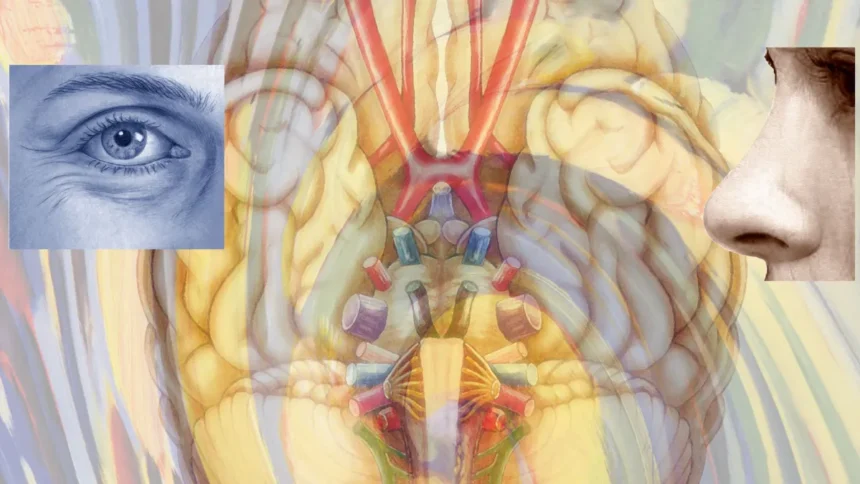

Az új módszer különlegessége, hogy ötvözi a hagyományos képalkotó eljárásokat (fMRI) a legújabb gépi tanulási algoritmusokkal. „A látás több mint a szemünk működése – valójában az agyunk az, ami ‘lát'” – fogalmazott Dr. Kovács Ildikó, a kutatócsoport vezetője. A Magyar Országos Levéltár tudománytörténeti gyűjteményében megtalálható dokumentumok szerint ez a felismerés már a XIX. század végén foglalkoztatta a magyar tudósokat, köztük Ranschburg Pált is, akinek pszichofizikai laboratóriuma a régió egyik első ilyen intézménye volt.

Az új eljárás lényege, hogy a kísérleti alanyok által látott képeket összeveti az agyukban ezzel egyidejűleg zajló aktivitásmintázatokkal. A mesterséges intelligencia ezekből az adatpárokból képes „megtanulni”, hogyan alakul át a vizuális inger neurális jelekké. A módszer megbízhatóságát igazolja, hogy a kutatók képesek voltak olyan képeket rekonstruálni, amelyeket a vizsgált személyek láttak, pusztán az agyi aktivitásmintázatok alapján.